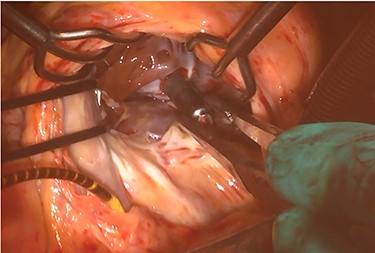

At his 1-year follow-up visit, the patient presented with shortness of breath on exertion and leg edema; thus, we decided to perform surgical correction. After median sternotomy, cardiopulmonary bypass was established with ascending aortic and bicaval venous cannulations. MyoPore (Greatbatch Medical, NY, USA) bipolar sutureless screw-in lead was attached to the left ventricle. A permanent PM was implanted, and left atrial appendage exclusion with AtriClip (AtriCure, OH, USA) was performed afterward. A right atriotomy was performed to facilitate exposure, wherein we found that the septal and posterior leaflets of the tricuspid valve were severely damaged (Fig. 3). Micra was placed over the right ventricular septum and was easily freed under direct vision (Fig. 4). After the leaflets were excised, an Epic (St Jude Medical, MN, USA) 33-mm bioprosthesis was implanted.

Intraoperative photograph; Micra was retrieved under direct vision.